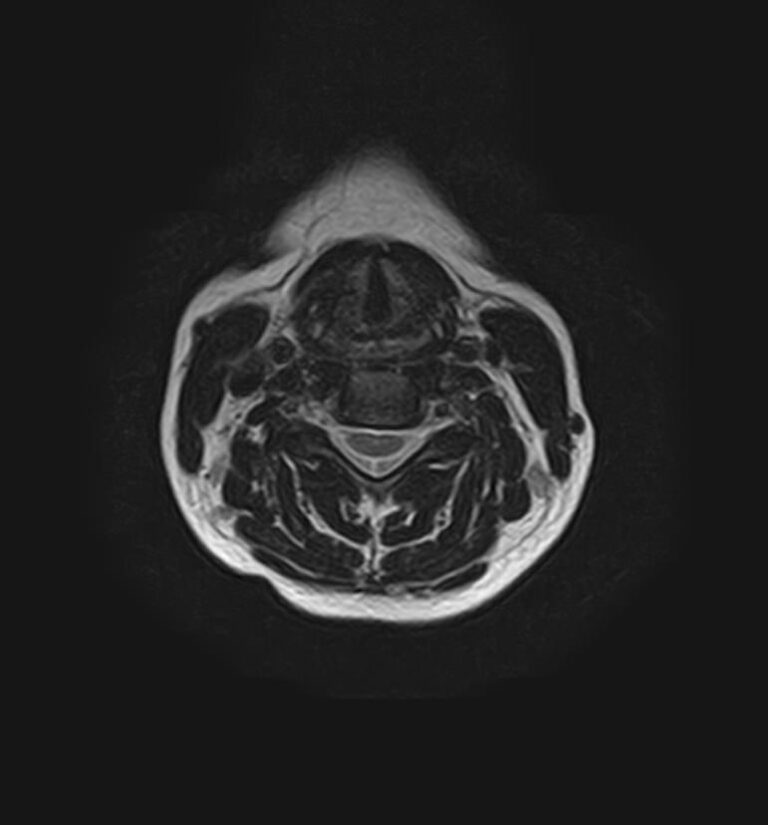

Шейный отдел позвоночника — это самый подвижный сегмент позвоночного столба, который испытывает повышенные нагрузки, подвержен травмам и развитию различных заболеваний. В эту анатомическую область входит 7 верхних позвонков, спинной мозг с отходящими от него нервными корешками.

Сканирование проводится на современном высокопольном магнитно-резонансном томографе закрытого типа TOSHIBA VANTAGE TITAN 1,5 Тесла. Магнитно-резонансный томограф производит послойное сканирование исследуемой зоны в разных плоскостях, затем при помощи компьютерных программ преобразует полученные данные в трехмерные изображения. При этом кровеносная система реконструируется как вместе с окружающими тканями, так и отдельно без них.

• остеохондроз, спондилоартроз, спондилез, межпозвонковые грыжи, унковертебральный артроз, сколиоз, усиленный или выпрямленный лордоз как нарушение статической функции позвоночника, травмы, аномалии позвоночника.